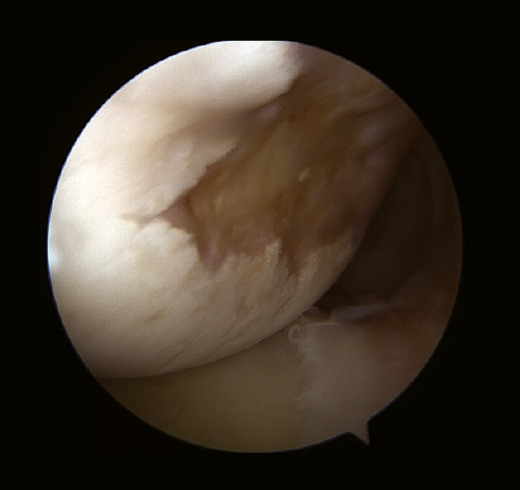

Burkhart y De Beer(19,20) enfatizaron el papel de la artroscopia como herramienta para el diagnóstico dinámico y definitivo de las lesiones “no enganchantes y enganchantes”, y la falta de una correcta interpretación de los defectos óseos era la causa de muchos fracasos en la reparación primaria de una IGH por error en la técnica quirúrgica adecuada.

Las mediciones on-track y off-track son valores comparables a los conceptos de “lesión no enganchante o enganchante” de Burkart et al.(19), la diferencia es que las primeras se miden con una 3D-TAC antes de la cirugía, permitiendo establecer la indicación de la técnica quirúrgica más apropiada antes de la cirugía (reparación de partes blandas vs. tope óseo), y la valoración de las lesiones “no enganchantes o enganchantes” se realiza artroscópicamente (Figuras 5 y 6).